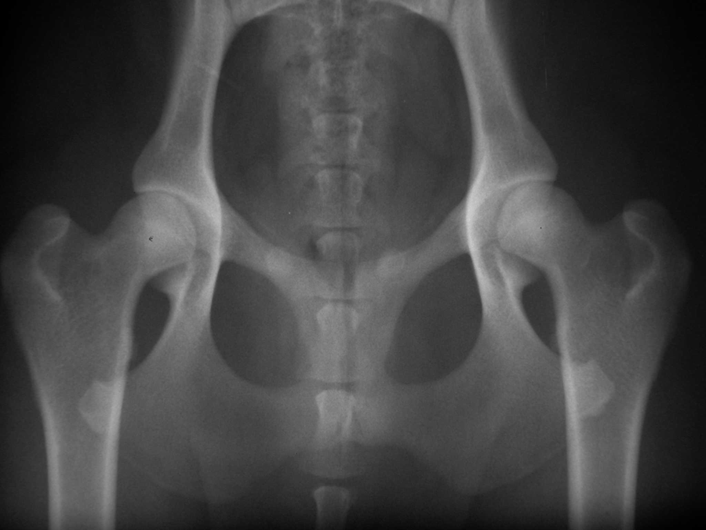

Abb. 2: Exzellente Hüftgelenke (Grad A) bei einem 15 Monate alten Labrador Retriever der Blindenführhundeschule Allschwil. Bei beiden Hüftgelenken sitzt der runde Oberschenkelkopf tief in der Pfanne. Der Vorderrand der Pfanne (oben) liegt dem Kopf exakt an, der Gelenkspalt ist schmal, der vordere Pfannenknochen gleichmässig schmal. Durch umfassende Nachzuchtkontrolle mit rigider Auslese der Zuchttiere aufgrund der Qualität der Nachkommen weisen weit über 90% der Hunde der Schule hervorragende Hüftgelenke (und Ellbogengelenke) auf.